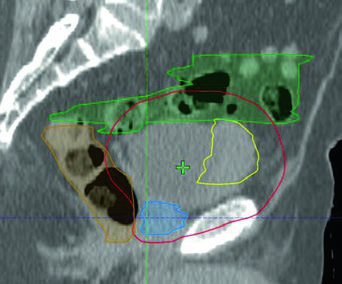

El caso ilustrado muestra quimiorradioterapia concurrente con IMRT bladder-only para un varón de 82 años con enfermedad músculo-invasiva irresecable en la pared anterolateral derecha de la vejiga. El PTV (rojo) se conforma al GTV (amarillo) protegiendo intestino (verde) y recto (naranja). Este tipo de abordaje resulta particularmente útil para pacientes ancianos o con performance status comprometido que se benefician de volúmenes menores y tratamientos más cortos.

El caso clínico ilustrado corresponde a un varón de 51 años con carcinoma urotelial cT2N+ localmente avanzado, con masa de 5,0 x 2,8 cm en la pared posterolateral izquierda, sometido a TURBT máxima. Las imágenes de planificación sagital y coronal demuestran cómo el PTV del SIB nodal (PTV 56,25) se superpone al campo pélvico inicial (PTV 45) sin comprometer excesivamente las estructuras adyacentes, con los fiduciales claramente visibles en el lecho de TURBT. En la fase de boost, el volumen se reduce al lecho de TURBT con margen conformado, permitiendo escalamiento seguro de dosis al tumor primario.